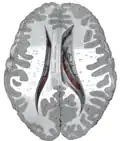

The caudate nuclei are near the center of the brain, sitting astride the thalamus. There is a caudate nucleus in each hemisphere of the brain. Each nucleus is C-shaped, with a wider "head" (caput in Latin) at the front, tapering to a "body" (corpus) and a "tail" (cauda). Sometimes a part of the caudate nucleus is called the "knee" (genu).[6] The caudate head receives its blood supply from the lenticulostriate artery; the tail of the caudate receives its blood supply from the anterior choroidal artery.[7]

The head and body of the caudate nucleus form part of the floor of the anterior horn of the lateral ventricle. The body travels briefly towards the back of the head; the tail then curves back toward the anterior, forming the roof of the inferior horn of the lateral ventricle. This means that a coronal section (on a plane parallel to the face) that cuts through the tail will also cross the body and head of the caudate nucleus.

Caudate nuclei along with other subcortical structures, in glass brain -